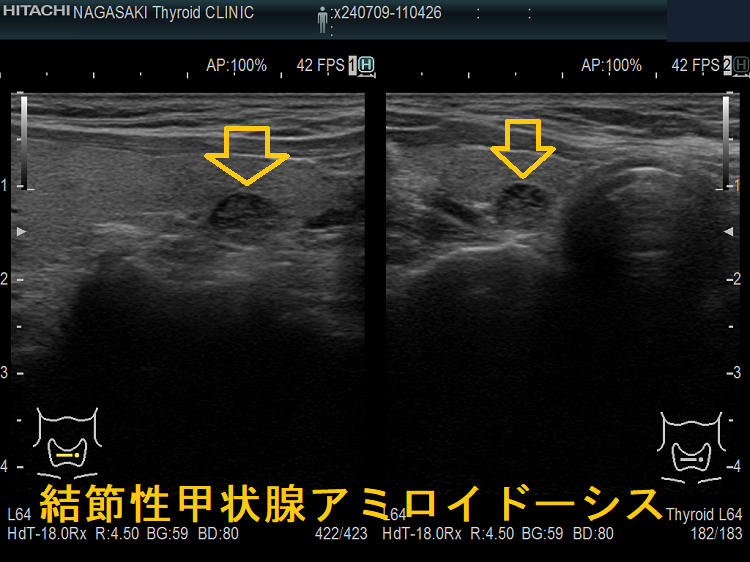

謎の結節性甲状腺アミロイドーシスを鹿児島大学が甲状腺学会で複数回、さらに大分大学も論文で報告しています。超音波(エコー)検査上、見かけは甲状腺腫瘍、境界不明瞭・不均質な低エコー領域で、石灰化も伴う。穿刺細胞診で腫瘍成分はなく、アミロイドのみが見つかるも、アミロイドーシスをおこす他の病気が全くないとの事です。

大分大学の報告は多結節性甲状腺腫の形態です[Acta Pathol Jpn. 1992 Mar;42(3):210-6.]。

橋本病に合併した結節性甲状腺アミロイドーシスの病理組織標本では、